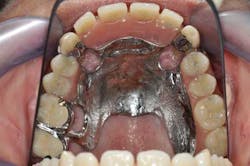

Figs. 6 a, b, c, and d: RPD framework try-in, bite record with mandibular implant-supported metal frameworks and mounting